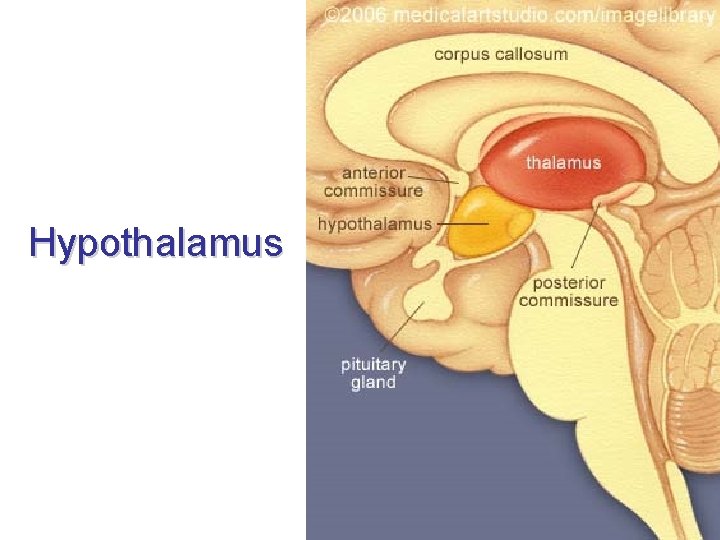

Hypothalamus

Hypothalamus • • je derivát visceromotorické zóny bazální ploténky nejvyšší autonomní ústředí infundibulum + hypophysis tuber cinereum (eminentia mediana) + corpus mammillare • area preoptica + chiasma et tractus opticus

Hypothalamus • infundibulum • tuber cinereum • corpora mammillaria • recessus infundibuli • recessus opticus

Hypothalamus – ohraničení • • nahoře: sulcus hypothalamicus dole: viditelný na dolní ploše mozku vpředu: lamina terminalis vzadu: přechází do tegmentum mesencephali • mediálně: 3. komora • laterálně: capsula interna